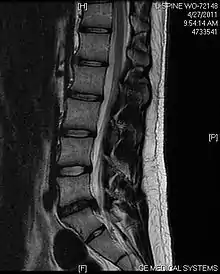

| فتق دیسک کمری در نمای امآرآی. | |

- ام آرآی: یکی از بهترین امکانات تشخیصی در فتق دیسک است. این روش میتواند ریشههای عصبی و نخاعی و بافتهای اطراف را به خوبی نشان داده و تغییرات را ثبت کند. در نمای T2 فتق دیسک نمایان میگردد.